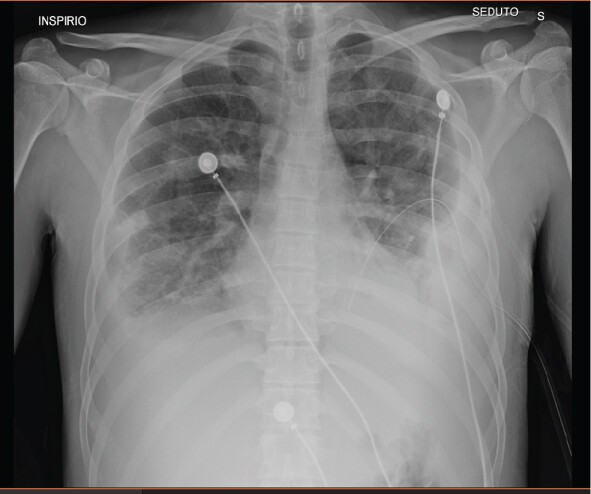

Рентгенография грудной клетки выявила двусторонний плевральный выпот и очаги уплотнения в обоих легких (рисунок 1). На КТ с контрастным усилением был подтвержден двусторонний плевральный выпот, более обширный справа (5,5 см против 3 см), множественные узлы в обоих легких без признаков ТЭЛА (рисунки 2-3). Также было отмечено тромботическое поражение правой внутренней яремной вены (рисунок 4).

Рис. 1. Рентгенограмма грудной клетки, на которой заметны легочные узлы и плевральный выпот.